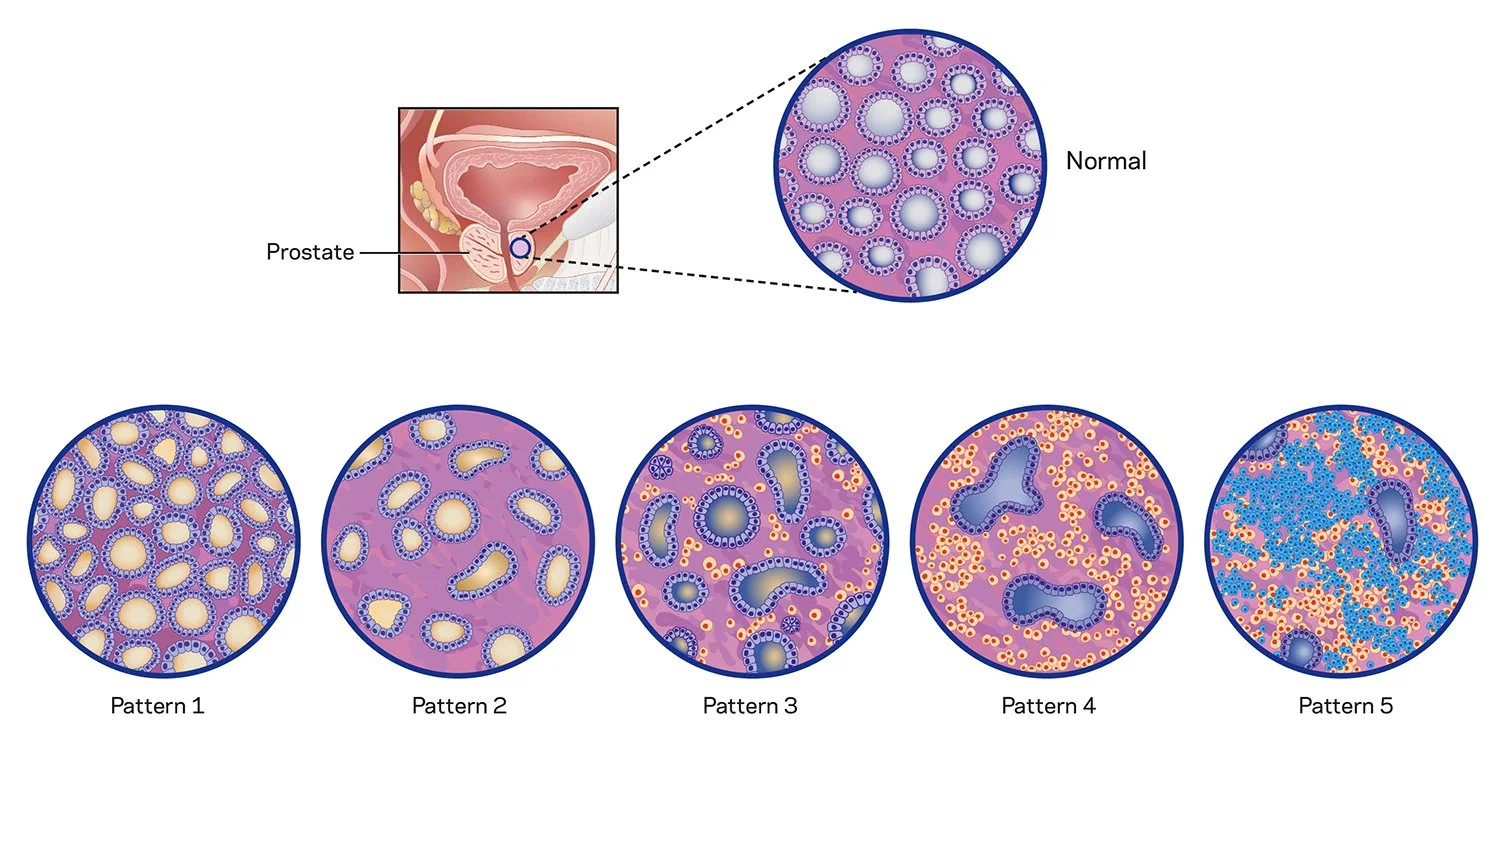

Surgical illustrations visually depict operative techniques, surgical anatomy, and complex procedures. They are created with high anatomical accuracy and serve as a visual bridge between complex surgical knowledge and learners, clinicians, or patients.

Prostate Cancer Booklet

Created clear, accurate, and visually engaging medical illustrations for a patient education booklet on prostate cancer for a hospital system. The illustrations simplified complex anatomical and clinical concepts, helping patients better understand diagnosis, treatment options, and disease progression.

Client: Northwell Hospital System

Patient Education: Prostate Cancer